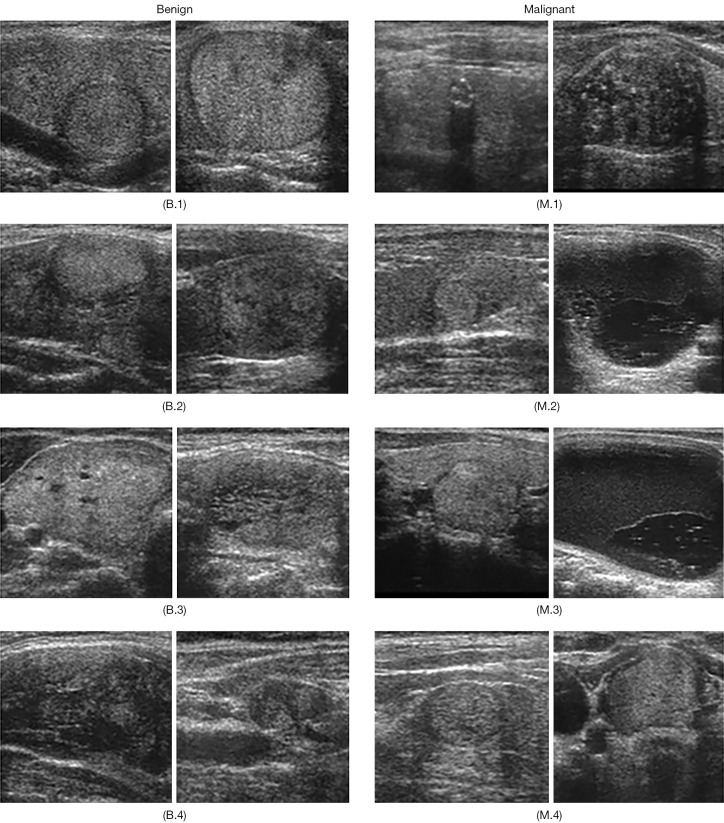

Background: The accurate assessment of thyroid nodules, which are increasingly common with age and lifestyle factors, is essential for early malignancy detection. Ultrasound imaging, the primary diagnostic tool for this purpose, holds promise when paired with deep learning. However, challenges persist with small datasets, where conventional data augmentation can introduce noise and obscure essential diagnostic features. To address dataset imbalance and enhance model generalization, this study integrates curriculum learning with a weakly supervised attention network to improve diagnostic accuracy for thyroid nodule classification.

Methods: This study integrates curriculum learning with attention-guided data augmentation to improve deep learning model performance in classifying thyroid nodules. Using verified datasets from Siriraj Hospital, the model was trained progressively, beginning with simpler images and gradually incorporating more complex cases. This structured learning approach is designed to enhance the model's diagnostic accuracy by refining its ability to distinguish benign from malignant nodules.